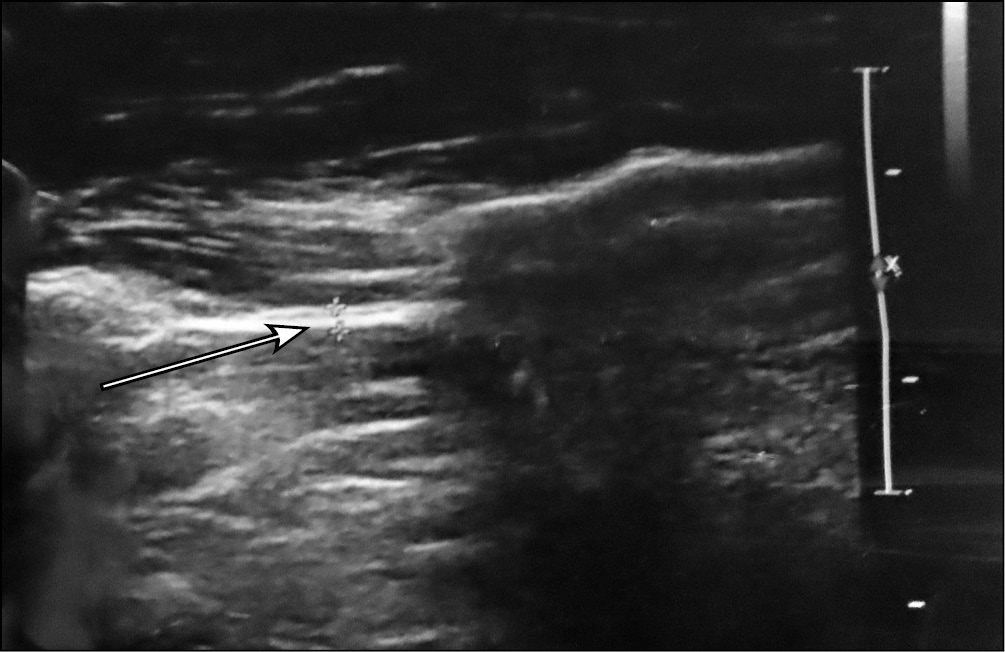

Дистальный отдел межкостной мембраны так же визуализируется, как гиперэхогенное образование. У людей, у которых отсутствует ДКП, толщина ДММП составляет от 0,3–0,7 мм в независимости от положения предплечья (рис. 8). Толщина же ДКП при УЗ-исследовании составляет от 0,9 до 2 мм также в независимости от положения предплечья (рис. 9). Среднее значение составляет 1,4 ± 0,5 мм. Из 30 обследуемых дистальный косой пучок был выявлен у 13 женщин (92,8 %) и 1 мужчины (7,1 %), что в процентном соотношении составило 43 %. Помимо ширины измеряли и длину ДКП, интервал длины у обследуемых составляет от 13 до 19 мм. Среднее значение 15,5 ± 1,9 мм. Изменение длины также не происходит независимо от положения предплечья.

Рис. 8. Ультразвуковое изображение дистального отдела межкостной мембраны предплечья — дистальный косой пучок не определяется

Рис. 9. Ультразвуковое изображение дистального отдела межкостной мембраны предплечья — дистальный косой пучок присутствует (показано стрелкой)